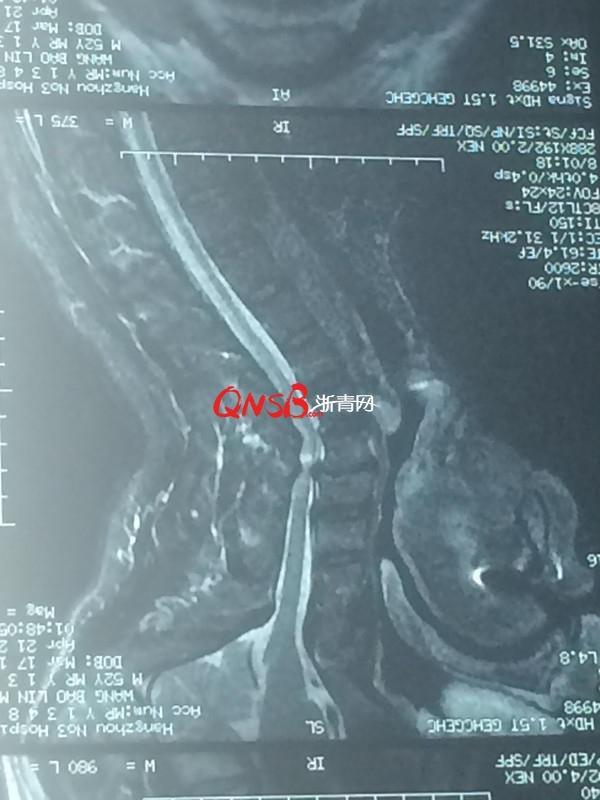

剛入院時,懷疑為中風在神經內科就診,顱內磁共振並未發現出血,2天後做了脊椎磁共振發現了問題,轉到骨科由瞿杭波負責,最後確診為脊髓型頸椎病伴不全癱,一種重度癱瘓疾病,接近全癱。

王大伯的影像學,能看到喉頸部有明顯斷層。

瞿醫生解釋道,王大伯的頸椎不僅全部受壓迫,壓迫程度非常厲害,且頸髓因為受壓直接導致水腫,神經裡麵都出血了。